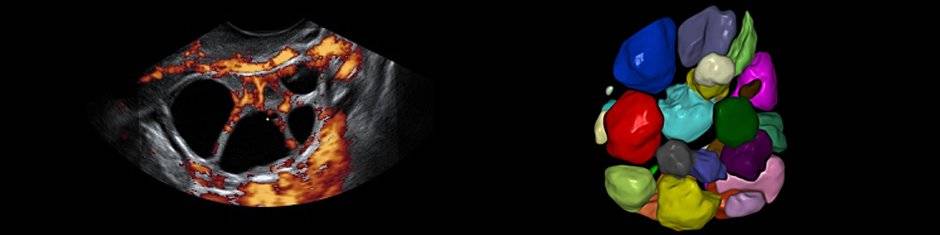

В нашем отделении каждый случай рассматривается отдельно целой группой профессионалов, специализирующихся в данной области. Наличие отделения низкого резерва яйцеклеток Института Бернабеу позволяет пациенткам пользоваться самыми актуальными инновациями для диагностики и лечения: тесты в специализированных авангардных лабораториях, гинекологическое УЗИ 4D для исследования сосудов яичников и матки, анализ генетических маркеров, матриксная сравнительная геномная гибридизация и другие исследования для разработки индивидуальной стратегии оптимизации возможностей достижения успеха для каждой конкретной пары.